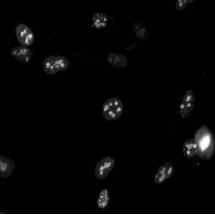

03場景圖/實拍效果圖

背照式顯微相機具有極高的量子效率。通常具有高達95%的量子效率,這意味著它們能夠?qū)⒏嗟墓庾愚D(zhuǎn)換成電子,從而提高成像的靈敏度。例如,廣州明美的背照式sCMOS相機MSH12-BI在波長560nm處量子效率達到了95%。這意味著即使是最微弱的熒光信號也能被MSH12-BI清晰地捕捉到。非常適合熒光顯微鏡下的低光照條件,有助于減少激發(fā)功率,保護活細(xì)胞,并減少熒光染料的光漂白。當(dāng)然,背照式顯微相機在低光照條件下工作時也可能受到噪聲的影響。而MSH12-BI通過半導(dǎo)體主動制冷的模式,將相機的讀出噪聲降至1.2e-,提供了更清晰的圖像。同時,背照式顯微相機具有高速成像能力。MSH12-BI提供了高達74fps的幀率,對于捕捉快速動態(tài)過程(如細(xì)胞遷移或神經(jīng)沖動傳播)非常重要。背照式相機采用較大的像素尺寸,這有助于提高單個像素的光收集能力,進一步增強了相機的靈敏度。